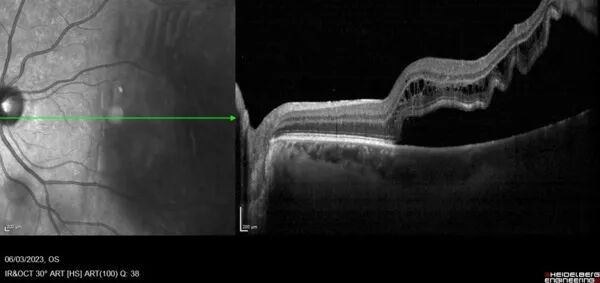

Le décolement de la rétine

Le décollement de rétine correspond à un soulèvement de la rétine. Ce décolement est souvent lié à une déchirure périphérique de la rétine. Les principaux facteurs de risque sont l’âge, la myopie, les antécédents traumatiques oculaires.

Les premiers signes cliniques de décollement de rétine sont : des flashes, des mouches volantes, un voile noir voire.Une baisse d’acuité visuelle immédiate y est associée.

Le décollement de rétine nécessite une prise en charge chirurgicale urgente.